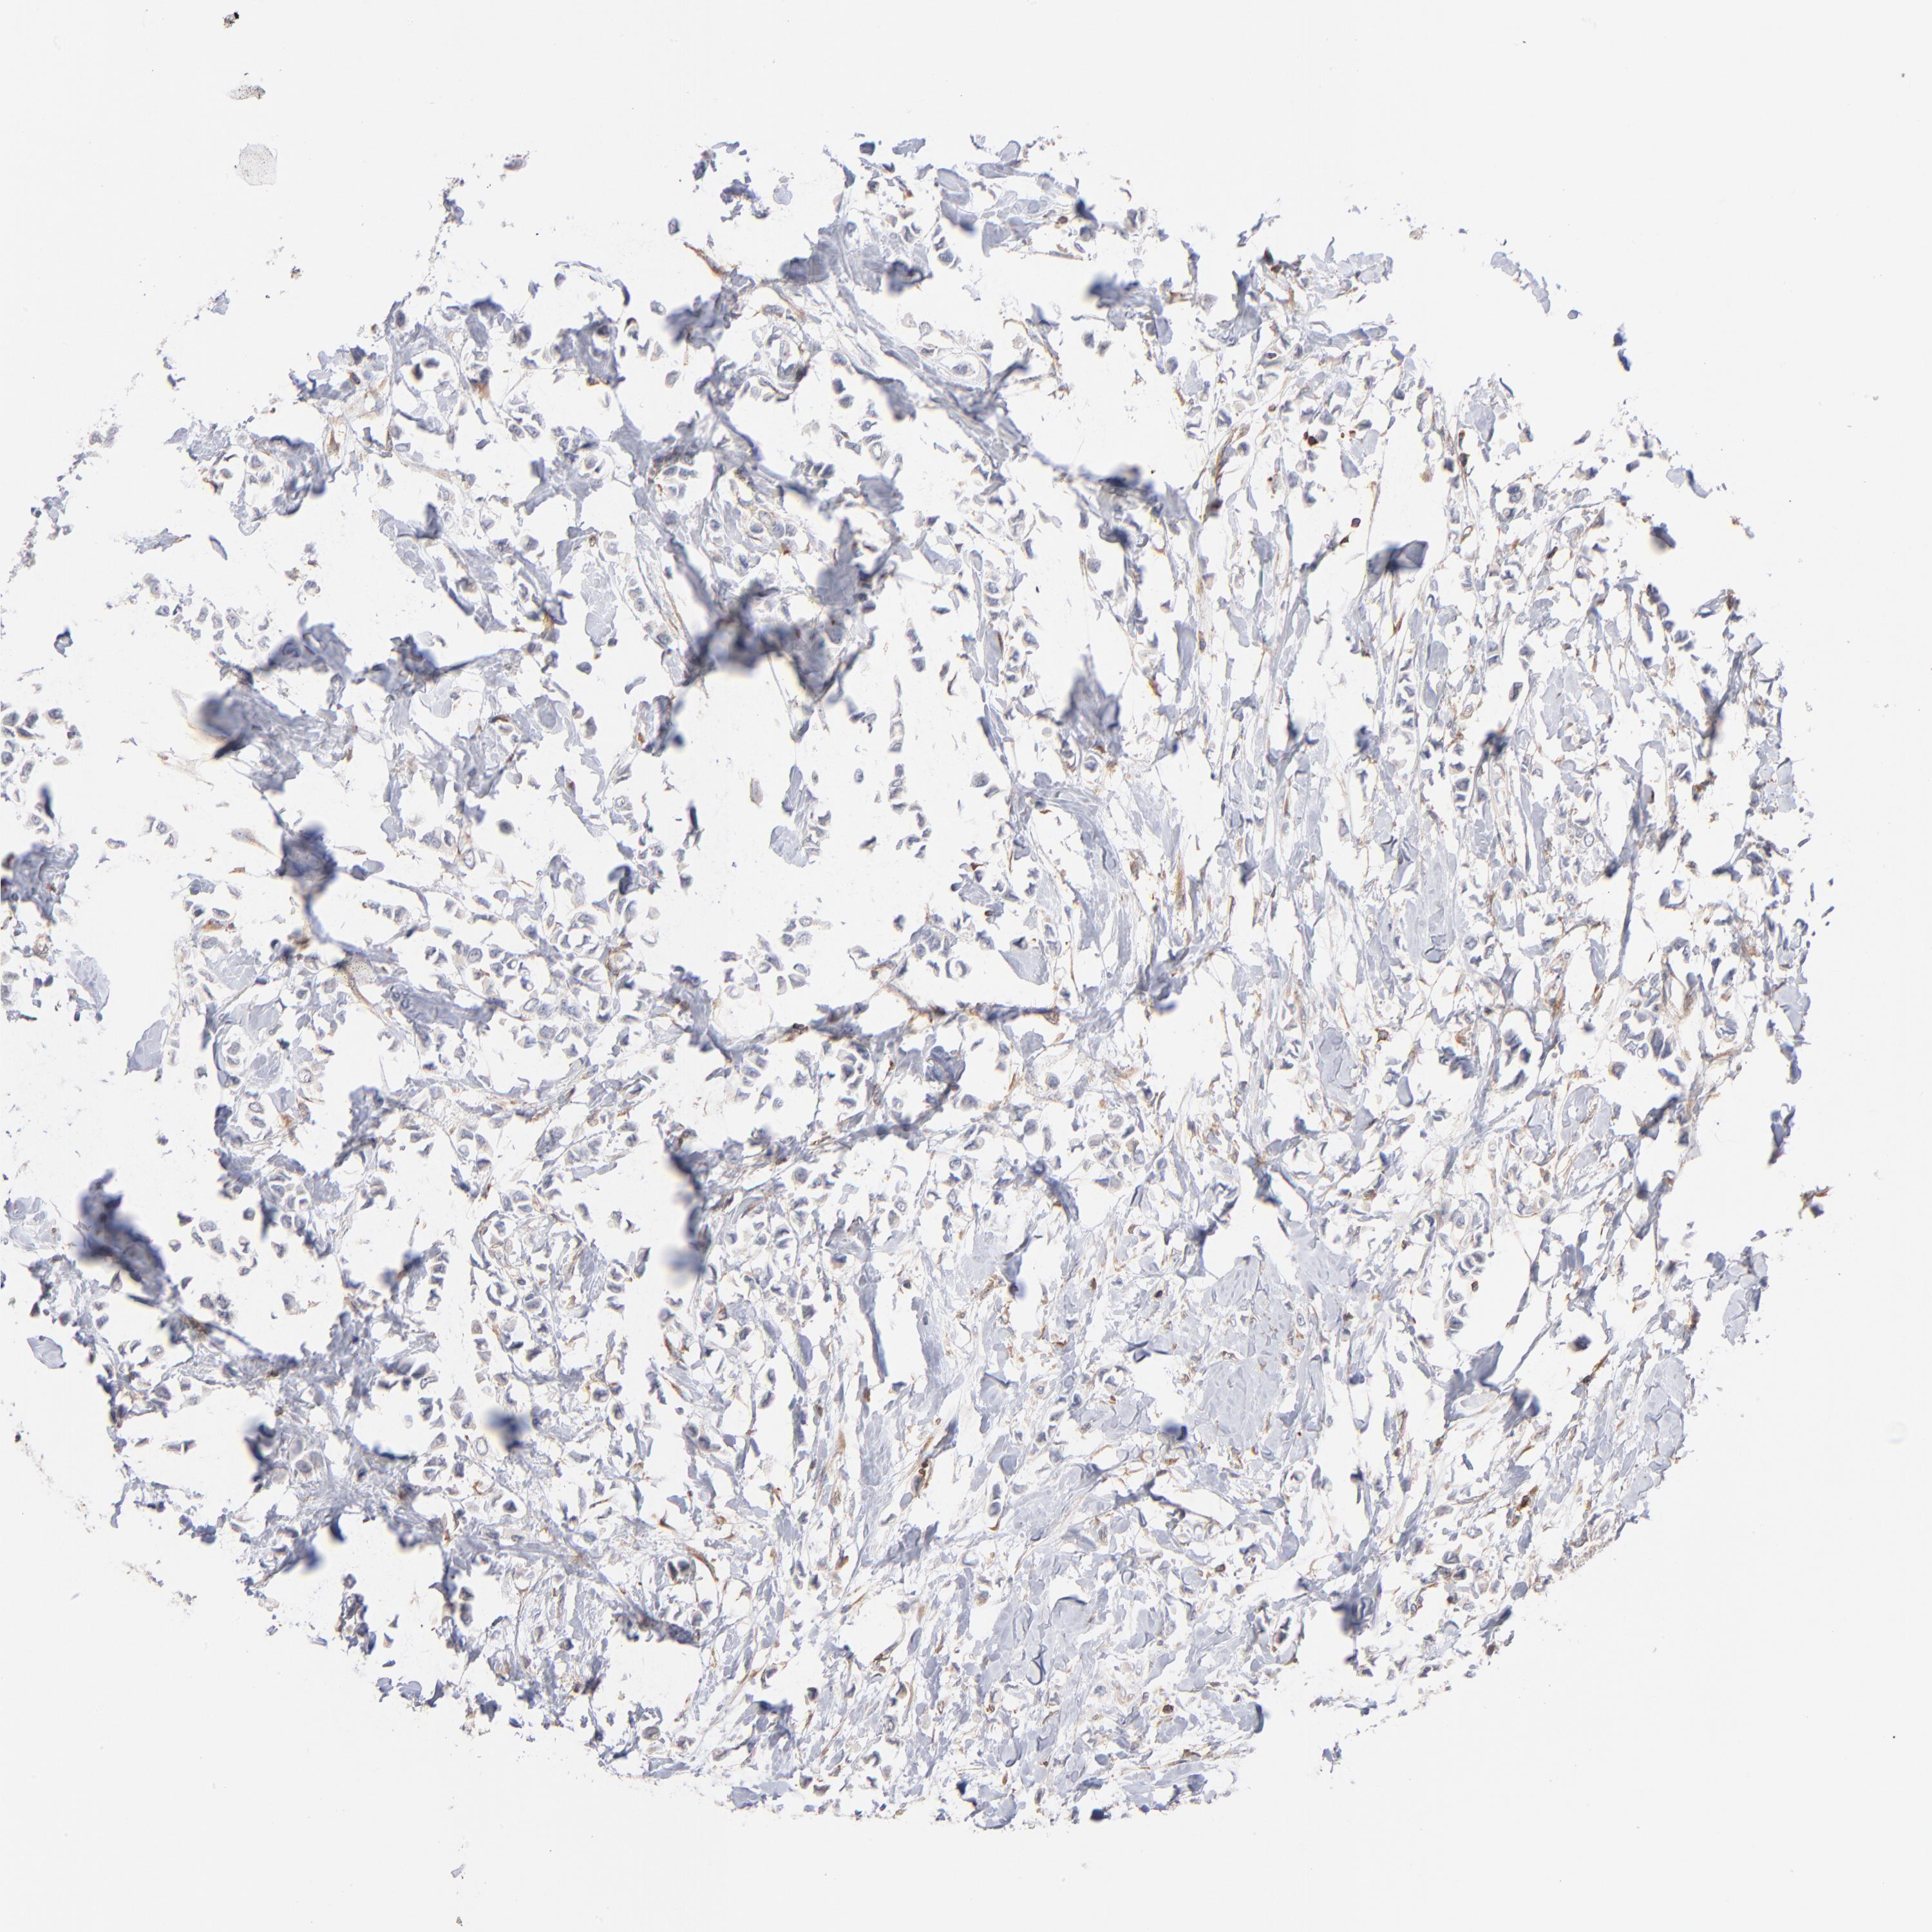

BRCA TCGA BRCA VALIDATION PROTEIN EXPRESSION

ANTIBODIES

AND

VALIDATION